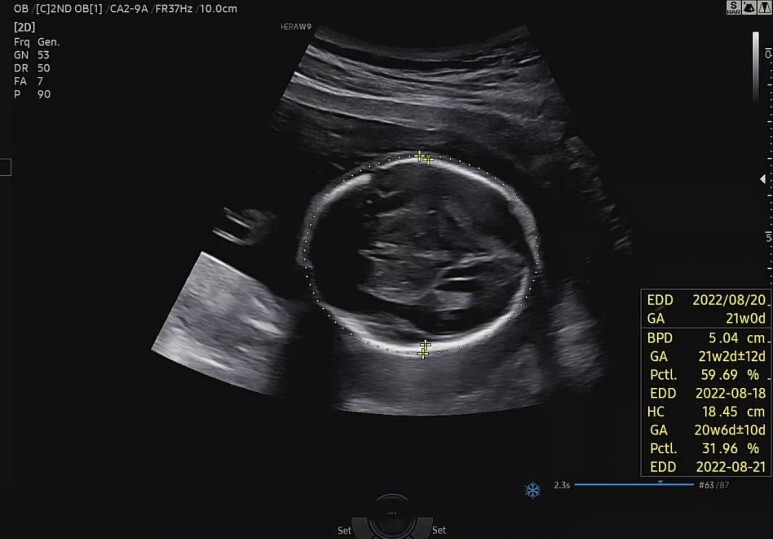

먼저 꿀잠이 머리둘레(BPD)와 직경(HC)